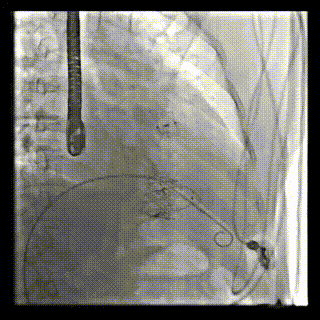

本周三例接受LuX-Valve Plus經(jīng)血管三尖瓣置換術(shù)的患者中,第一例患者為冠狀動脈旁路移植術(shù)+Bentall+二尖瓣成形術(shù)后;第二例患者為永久起搏器植入術(shù)后,存在跨三尖瓣導(dǎo)線;第三例患者合并房顫、房缺及左心耳封堵術(shù)后。

三例患者入院后,葛均波院士團隊周達(dá)新教授、潘文志教授、張源博士、陳莎莎博士及心超室的潘翠珍教授、李偉教授對患者的情況進行詳細(xì)評估和討論,最終決定為三例患者選擇LuX-Valve Plus40mm、50mm和50mm型號的瓣膜進行手術(shù)治療。手術(shù)后即刻拔除氣管插管,術(shù)后患者三尖瓣反流癥狀得到顯著改善,復(fù)查心超結(jié)果顯示人工三尖瓣瓣膜支架固定穩(wěn)定,瓣葉關(guān)閉形態(tài)未見異常,未見明顯反流。